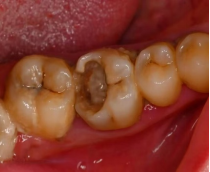

25岁的张先生长期在刷牙时出现牙龈出血,一直误以为是“上火”所致,偶尔使用漱口水缓解,从未进行过洗牙。一年后,他发现牙龈明显红肿,口臭加重,甚至在咬苹果时感到牙齿松动,来到了西安市红会医院口腔科就诊。经医生检查发现,张先生牙龈下堆积了大量牙结石,牙槽骨已出现吸收(牙齿“根基”变浅),最终被诊断为中度牙周炎。需通过“龈下刮治”清除深层结石,后续还要定期复查,否则牙齿可能进一步松动甚至脱落。

医生提醒:牙龈出血是牙周病的“早期信号”,并非“上火”,及时洗牙(每年1-2次)可预防;若拖到牙周炎,牙槽骨吸收不可逆,治疗难度和成本都会大幅增加。